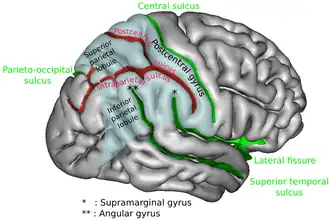

The superior parietal lobule is bounded in front by the upper part of the postcentral sulcus, but is usually connected with the postcentral gyrus above the end of the sulcus. The superior parietal lobule contains Brodmann's areas 5 and 7.

Behind it is the lateral part of the parieto-occipital sulcus, around the end of which it is joined to the occipital lobe by a curved gyrus, the arcus parietooccipitalis. Below, it is separated from the inferior parietal lobule by the horizontal portion of the intraparietal sulcus.